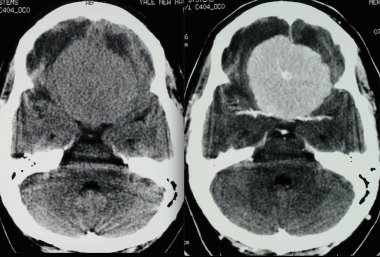

Псаммоматозная менингиома. КТ-исследование кальцифицированного объемного образования, обнаруженного на рентгеновском снимке. На томограмме, полученной на уровне верхней границы орбит, видна опухоль в области решетчатой пластинки (в области ольфакторной ямки).

З адняя тенториальная менингиома на корональном КТ-изображении с контрастным усилением. К намету мозжечка прилежит объемное образование повышенной плотности с четкими краями. Визуализируются застой спинно-мозговой жидкости, легкий отек прилежащих тканей, гомогенный характер контрастирования, а также расширение желудочков.